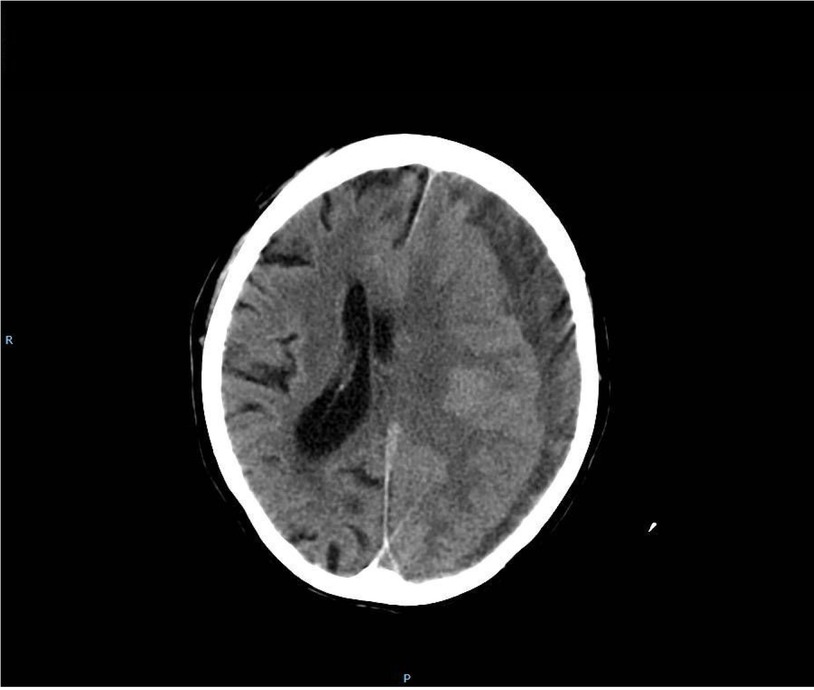

Image guidance diagnosis is done with CT-SCAN which shows a collection of blood in the Subdural space. Below is a CT-SCAN of a normal brain (R) and one with chronic Subdural haematoma (L)